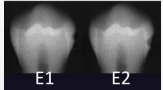

according to the ADA caries classification system, what is E1

outer ½ of enamel

according to the ADA caries classification system, what is E2

inner ½ enamel

classify this according to radiographic presentation of the ADA

E1

classify this according to radiographic presentation of the ADA

E2